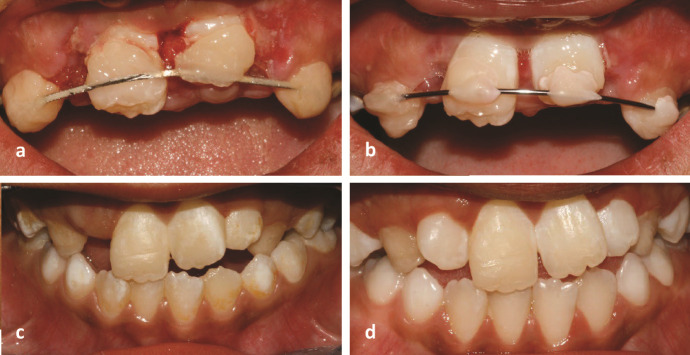

While traumatic injuries in the young permanent dentition are frequent, root fractures are relatively rare, particularly in immature teeth. This study reports the case of a 7-year-old boy who fell off a bicycle. Radiographic examination showed an immature right upper central incisor with fractures in the middle and along the root in an oblique and horizontal direction. Furthermore, there was an extrusion of the coronal segment from its original position. At the first appointment, the right central incisor was repositioned, and a semi-rigid splint was applied for four weeks. The patient was examined periodically for the following two years. After two months, the injured tooth was asymptomatic, with a reduction in probing depth from 8 mm to 2 mm along the tooth surface and a physiologic mobility. Although the injured tooth responded to the electric pulp test after nine months, it had no response to the cold test even after two years. The injured tooth showed continued root maturation of both coronal and apical fragments, although metamorphosis calcification and root canal narrowing were observed in conjunction with mild yellow crown discoloration. This report highlights the ability of Hertwig's epithelial root sheath and immature pulp to continue root development in fractured immature teeth.